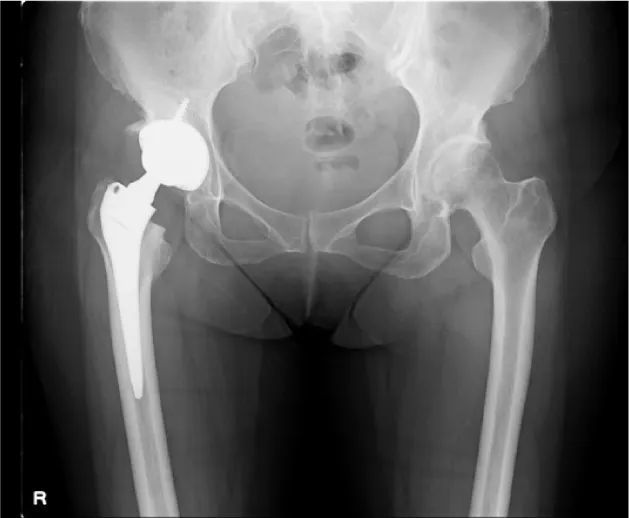

現在は手術後20年経過しても、約80%の患者さんで入れ替えが不要と言われています。当院では膝関節同様、手術前に撮影したCTを元に、3次元的な術前計画を行い、個々の骨形態に対し適格な設置位置を確認しています。さらに術中簡易ナビゲーションを使用し、より正確な設置ができるよう心がけています。人工股関節手術は骨を扱う手術のため、術中に骨から出血を起こします。

当院では、手術中に出血した血液を回収し、専用の機器で不純物を取り除き、洗浄した後に輸血をする、術中回収式自己血輸血を導入しています。この方法により、いわゆる通常の輸血を行う頻度を減らすことができます。

• 術後レントゲン